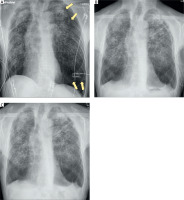

Figure 1

Serial chest radiographs. A – On admission, showing a large left-sided pneumothorax (arrows). B – Immediately after thoracoscopic pleurectomy, demonstrating lung re-expansion and satisfactory postoperative result. C – At discharge, showing complete resolution with no residual pneumothorax